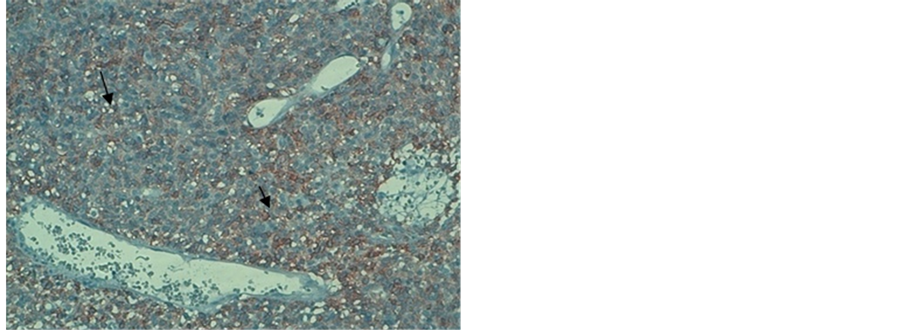

A liver biopsy of the mass showed a gastrointestinal stromal tumor with high risk of malignancy. Immunohistochemistry has revealed a positive CD 117 and CD 34, PS100 and AML (Figure 4).

Figure 4. Immunohistochemistry. (a) positive immunohistochemistry for the CD117; (b) positive immunohistochemistry for the CD34.